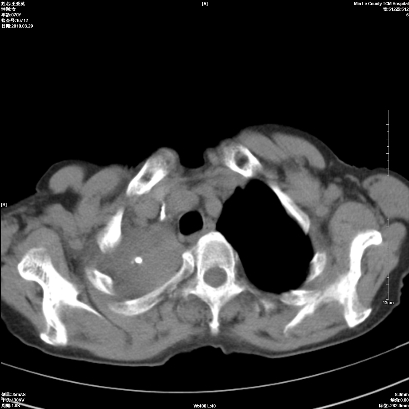

标题: CT25424:女性,70岁,胸闷、咳嗽月余。 [打印本页]

标题: CT25424:女性,70岁,胸闷、咳嗽月余。

右肺上叶支气管开口阻塞,上叶呈不均匀致密影,右肺中下叶内见斑片状密度增高影,上叶见钙化点,纵隔内见钙化淋巴结,桶状胸,右下肺动脉增粗,残根征,意见:1.右肺中心性肺癌;2.右肺陈旧性结核;3.肺心病。

ct所见:右肺上叶肺不张,呈软组织密度影向肺门区聚拢,其内可见含气段支气管及细支气管影,病灶内尚可见钙化结节。右肺上叶支气管狭窄,段支气管壁可见钙化。右肺下叶背段、右肺中叶见不规则小片絮状影及纤维条索影,形态较僵硬。右肺中叶胸膜旁可见多个小结节影。纵膈内见钙化淋巴结。

分析:右侧胸廓及右肺体积缩小,说明病变时间比较长了,应该是有数年的时间了,如果是短期内出现的肺不张,只会引起纵膈向患侧移位,而不会引起胸廓的塌陷。不张的肺组织内可见含气支气管影,说明右肺上叶支气管没有完全中断,只是狭窄。右肺中叶、下叶散在不规则病灶,部分呈纤维化改变。纵膈内的淋巴结大部分钙化。因此,本例给我的感觉良性病变的可能是大。

结论:考虑右肺上叶支气管内膜结核合并右肺上叶肺不张;右肺中叶、下叶陈旧性肺结核改变。